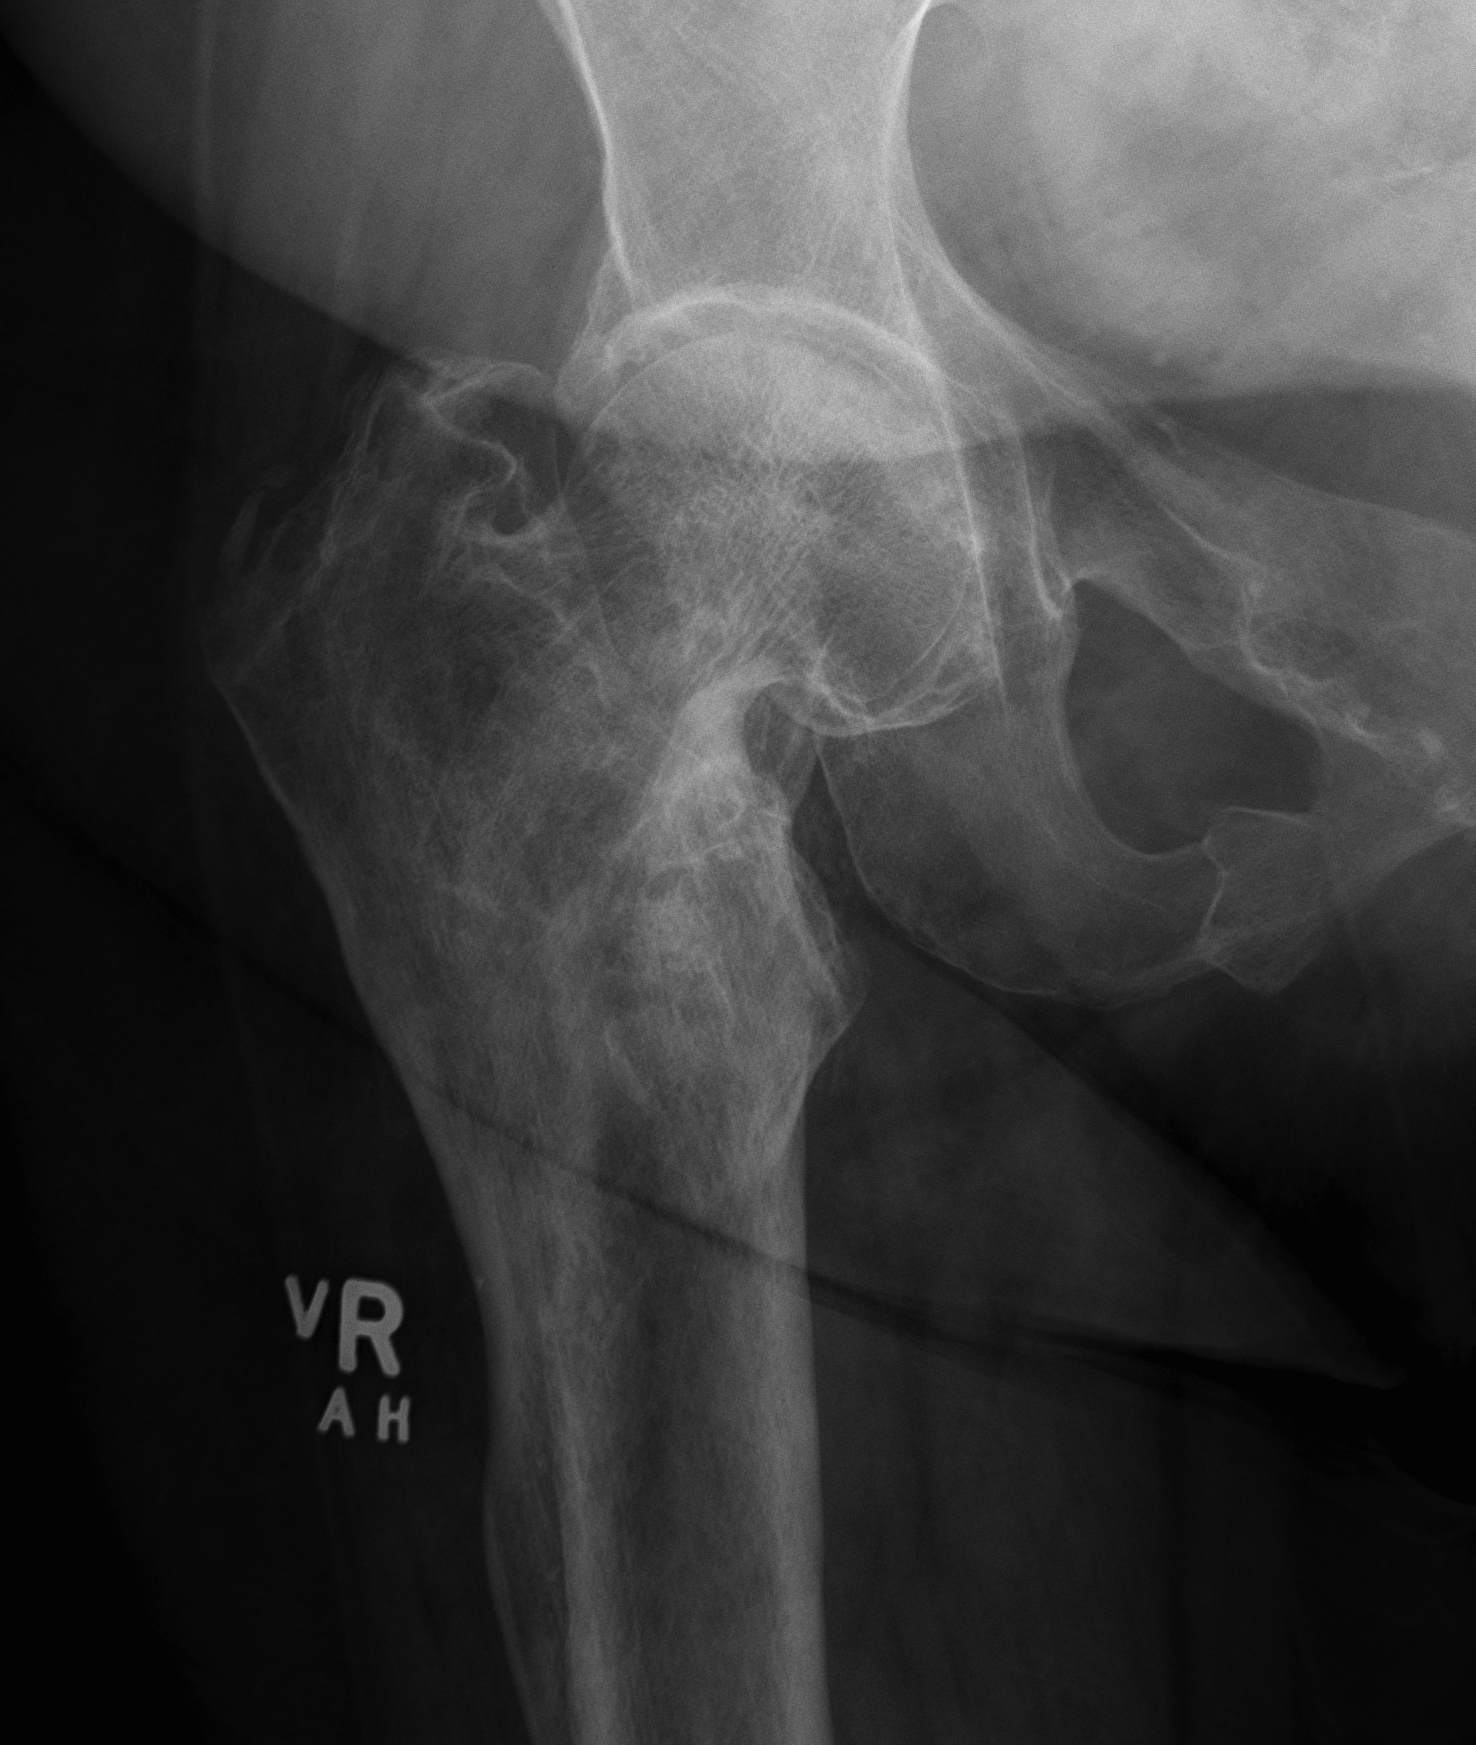

SUFE Perthes

DDH Protrusio

Trauma

Paget's AVN